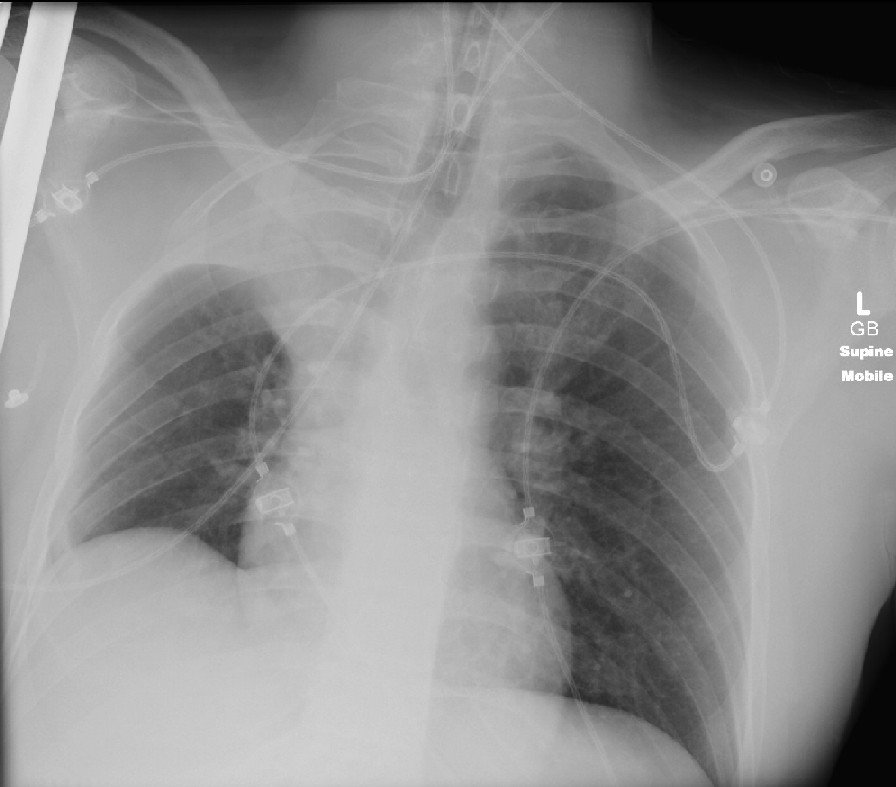

Male, 32, found near nightclub, GCS 5. Intubated and taken to hospital. Low sats and "grotty" looking sputum What does the X-ray show? List 3 possible causes What management would you implement? https://www.osler.community/cxr-quiz-3

#emergencymedicine#juniordoctors#interns#intensivecarepic.twitter.com/HrH61BV6ok